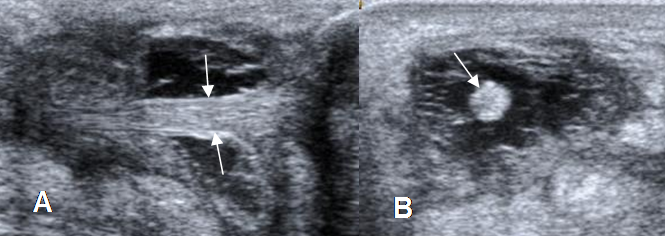

Fig 84. Ruptura parcial del aquiles.

A: Ecografía vista sagital y B: vista axial. Adelgazamiento del tendón por ruptura parcial, el cual está rodeado por líquido.